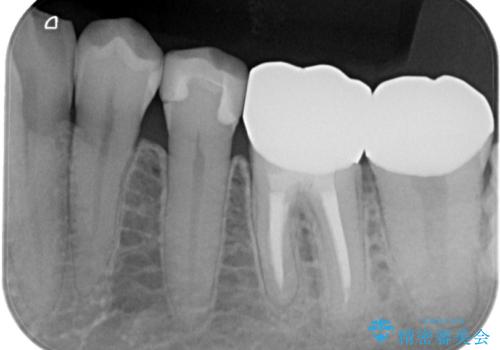

左下6はメタルクラウン、左下7はメタルアンレーがあり、左下5には虫歯がありました。

左下5はセラミックインレー修復、左下6,7はオールセラミッククラウンにて修復していくこととしました。

左下6に関しては、メタルコアをファイバーコアへのやりかえ、やりかえの際根管の汚染が強かったため根管治療からやりなおすこととなりました。